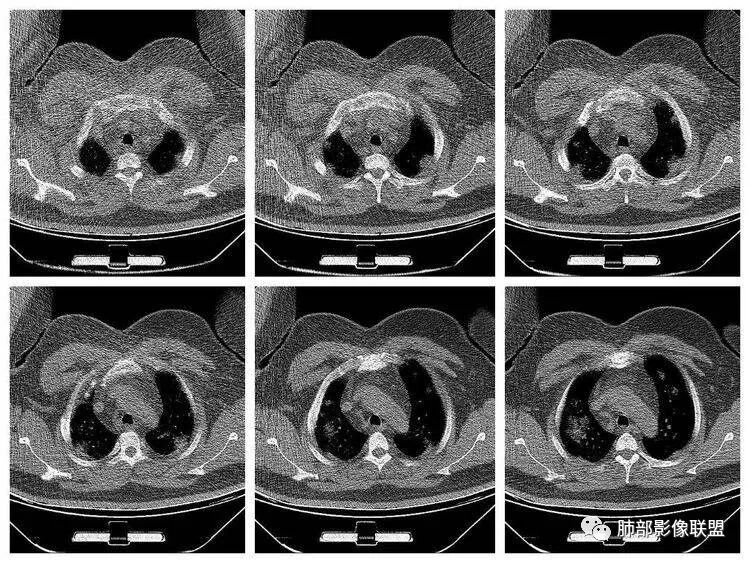

青年男性、急性病史、发热、咳嗽、常规抗炎无效病灶沿支气管血管束分布  GGO+实变边界模糊部分沿胸膜下分布哪几种可能?

南边:1、感染:间质分布——病毒、支原体,支原体一般树芽征明显,累及小气道多,而且临床轻,不太支持2、血管炎,需要相关病史3、肺水肿:心脏不大,无胸水、无中央间质增厚、小叶间隔增厚,不太支持4、PAP,病史影像表现都不支持初学者:可能是病毒,但是好像并不是我们常见的流感病毒实变为主,腺病毒?就是太多灶了一点

起病突然,高热,双肺多发磨玻璃影及实变影,胸膜下分布为主,不具有肺门分布优势,也没有小叶间隔增厚,一般会首先考虑病毒感染,尤其是甲流。